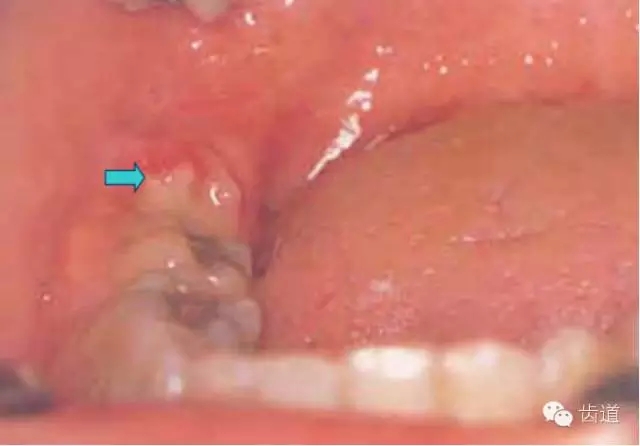

1.智齒萌出不全

2.牙冠周?chē)浗M織紅腫、糜爛、觸痛

3.齦瓣處形成盲袋,內(nèi)有膿性分泌物,有時(shí)形成冠周膿腫

4.嚴(yán)重時(shí)可見(jiàn)咽側(cè)壁及舌腭弓紅腫,患側(cè)頜下淋巴結(jié)腫大、壓痛。